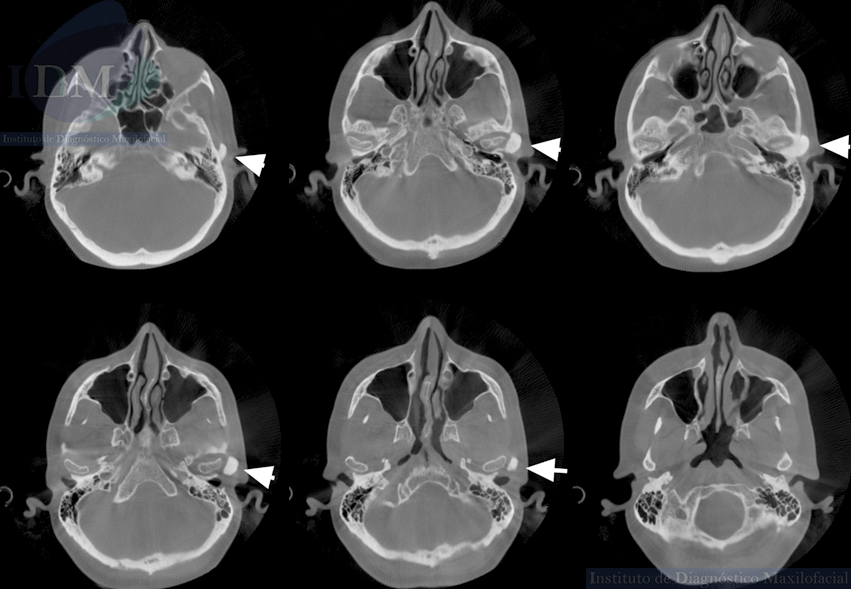

Al observar la tomografía volumétrica de haz cónico (en las reconstrucciones multiplanares, vistas transaxiales y tangenciales) se evidencia la misma imagen de forma redondeada y de densidad ósea que se localiza en la zona infratemporal y en la región posterior del arco cigomático izquierdo próximo a la cavidad glenoidea que a su vez estaría ocasionando un aplanamiento del contorno condilar en su cara externa.

CORTES AXIALES